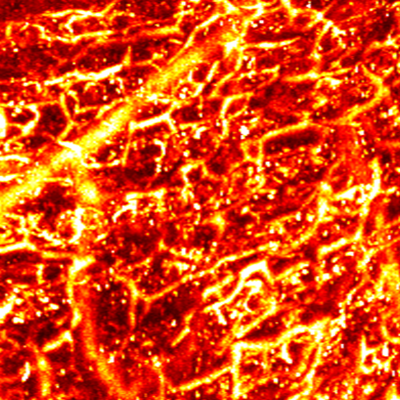

Layer by layer visualization of subdermal microvessels and pigments

MAP

Cross sectional view

Surface(Depth) view